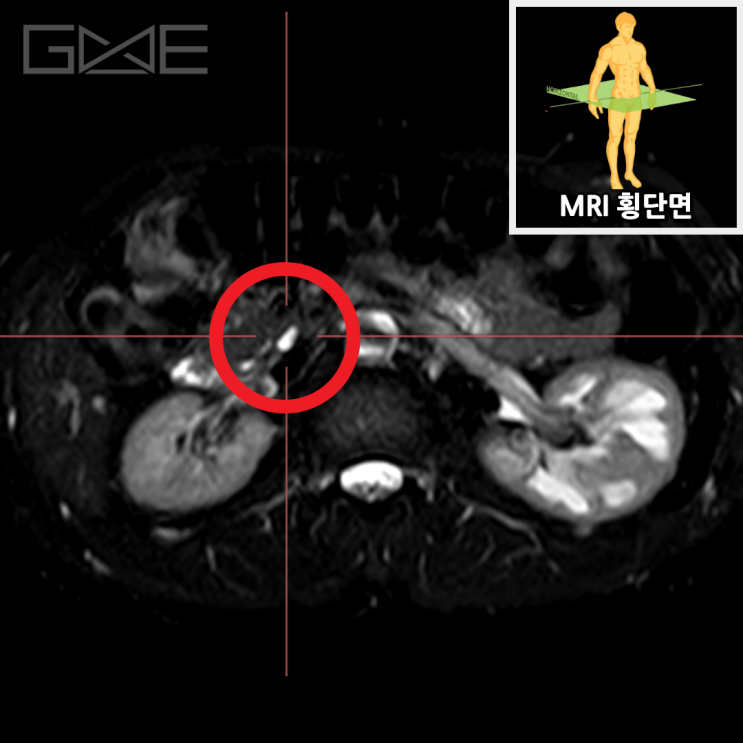

자기공명담췌관조영술상에서 췌장구상돌기 쪽으로 약 1.1cm 가량의 물혹이 보이고 있으며, 이는 췌장담도와 연결성이 보이고 있습니다. 이에 췌관내유두점액낭종으로 생각이 되며, 이에 대해서 추적 관찰을 하기로 하였습니다.

• 췌장MRI 횡단면: 물혹 확인(빨간 동그라미) 췌장MRI 횡단면: 물혹 확인(빨간 동그라미)